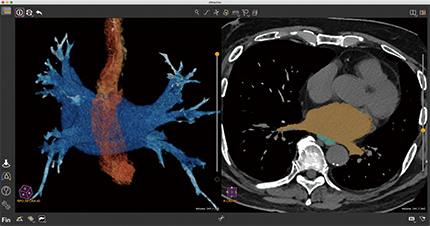

最新の画像診断装置からつむぎ出される膨大なデータの中には、体内の臓器や筋肉の働きが、想像を遥かに超える多様さ、詳細さで記述されています。このデータのどこをどう見たい、どう使いたいかは、臨床の現場で活躍するユーザーの皆さまそれぞれに少しずつ違います。医用画像解析アプリケーション「Attractive」は、その小さくて大切な「こだわり」に可能な限り柔軟に、確実に応えることで、日々の診断効率や精度の向上に貢献します。

Basic 3D